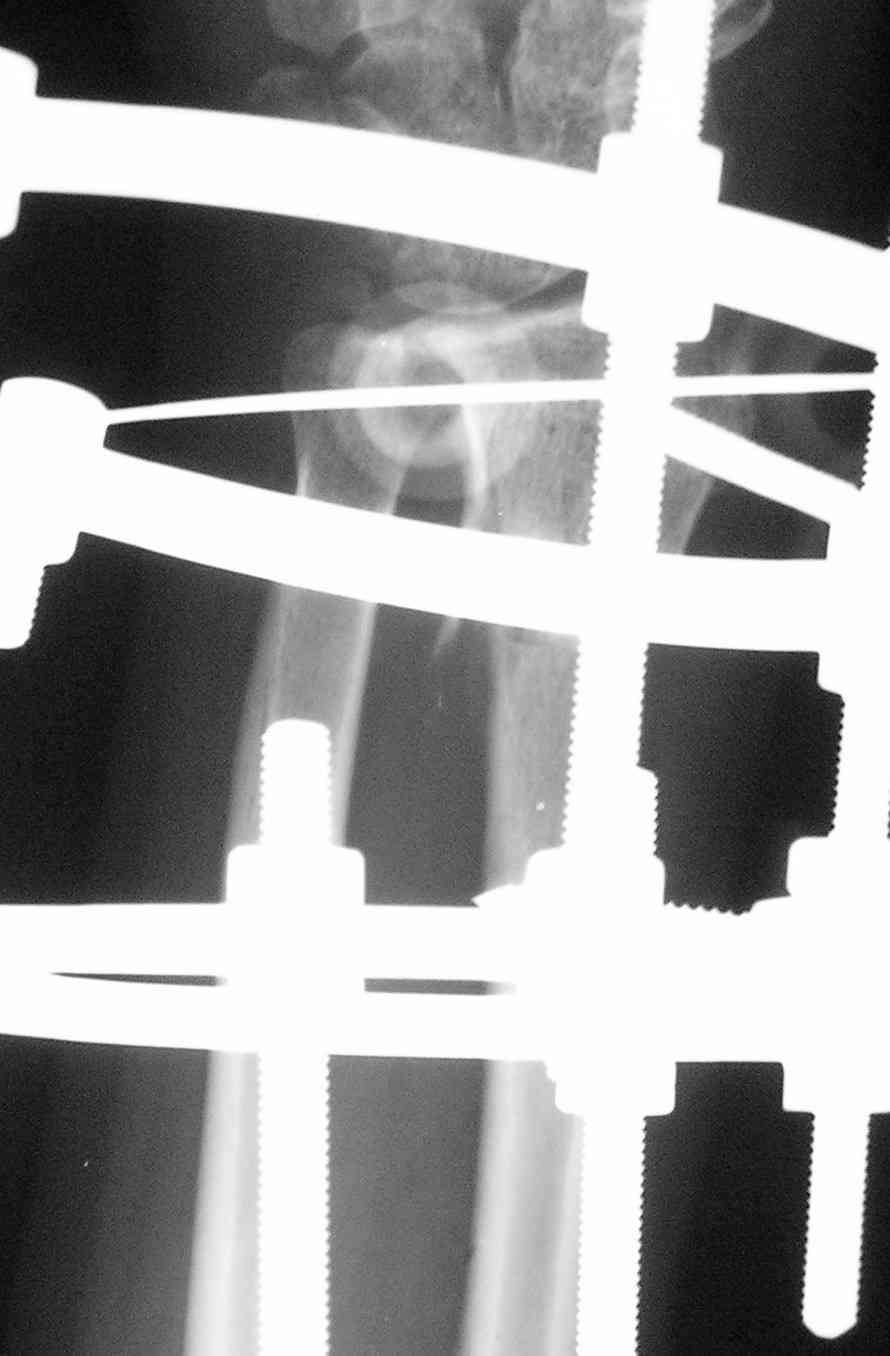

[Ortho] Последствия травмы предплечья

Спице-стержневой   аппарат   с  компактотомией  лучевой  кости,

костная  пластика  локтевой с  удалением  пластины. Не  комфортно,  но

больше  шансов  на  благоприятный  исход. Заканчиваю  лечение  с

похожей  деформацией  лучевой  кости.